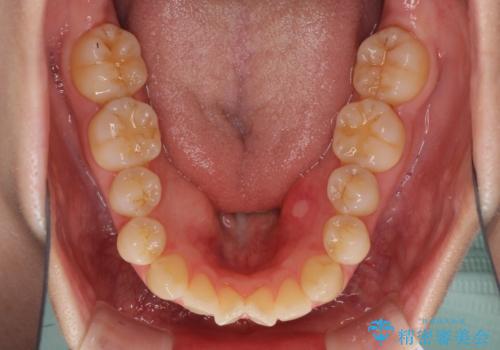

前歯の叢生とオープンバイト インビザラインでの矯正治療

- 前歯の開咬を気にして来院された患者様です。

開咬の治療は、前歯を閉じるように動かすとともに、上下臼歯を圧下(骨内にめり込ませる)させることで進めて行きます。

オープンバイトは舌の突出癖により誘発され、治療後も突出癖が残っている容易に後戻りしてしまいます。

治療期間を短縮するためにも、舌突出癖の改善が極めて重要となります。